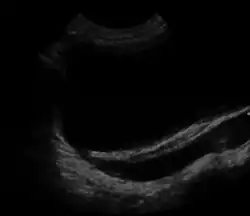

| Ultrasound image showing abnormal vesicoureteral junction and dilated distal ureter resulting in primary vesicoureteral reflux (VUR). | |